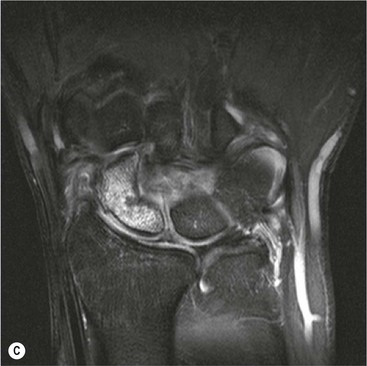

Abnormal communication between the radiocarpal and midcarpal joints may be seen on arthrography (Fig. 46-28), which is usually combined with MRI or CT16 (Figs. 46-29 and 46-30). However, direct visualisation of the ligaments is possible with conventional MRI. The most important features to describe that help determine management include the following:

The TFC is composed of fibrocartilage and is normally low SI on all MRI pulse sequences (Fig. 46-31). Tears of the TFC complex may present as ulnar-sided wrist pain. They occur as either a degenerative phenomenon or as an acute injury. Degenerative tears frequently result in central perforation of the TFC (Fig. 46-32), and are associated with positive ulnar variance (long ulna). This in turn may lead to ulnar abutment on the triquetrum, which is another cause of ulnar-sided wrist pain.

Traumatic TFC tears often affect the ulnar attachments and are associated with ulnar styloid fractures (Fig. 46-33). These injuries may also involve the dorsal and volar radioulnar ligaments and can lead to DRUJ instability.